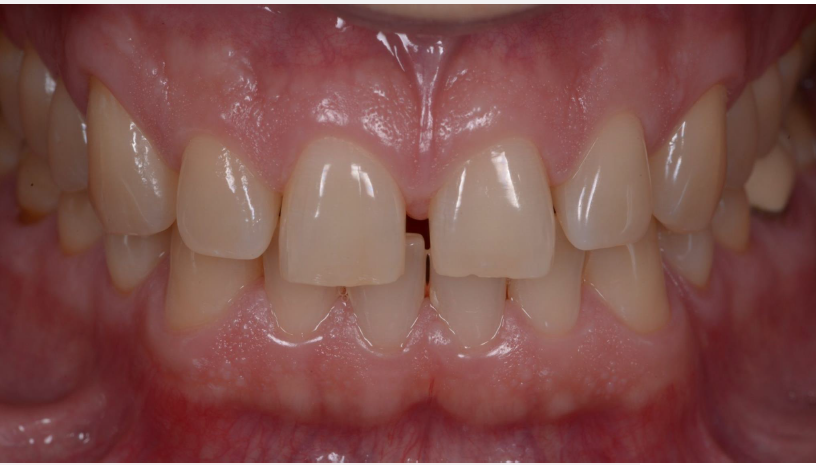

Close-up of teeth

Initial situation in the static occlusion.